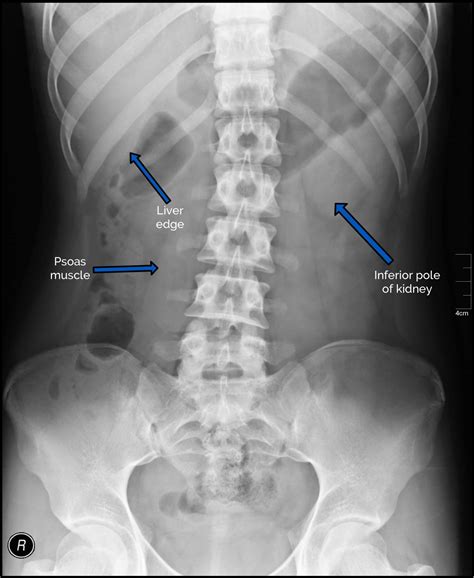

Interpreting the results of a Belly X Ray requires specialized training and expertise. Radiologists analyze the images to identify any abnormalities or signs of disease. Common findings include:

Radiologists may also use the images to assess the size and shape of organs, such as the liver, spleen, and kidneys, to detect any abnormalities.